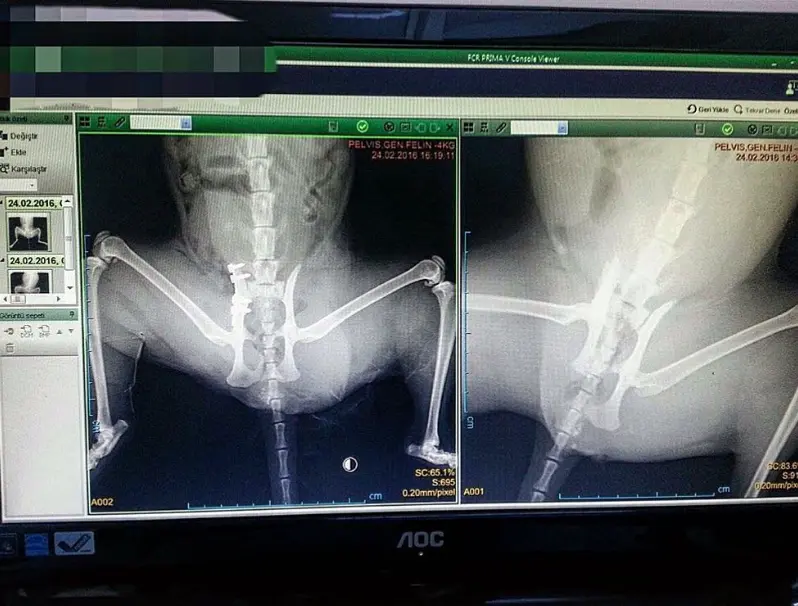

Ortopedik vakalarda ve travmatik yaralanmalarda, standart röntgen görüntüleri bazen yetersiz kalabilir. İki boyutlu görüntülerde kemiklerin üst üste binmesi (süperpozisyon), mikro çatlakların veya eklem içi hasarların gözden kaçmasına neden olabilir.

Acil travma vakalarında zamanla yarışıyoruz. Kliniğimizin Dijital Röntgen Sistemi, saniyeler içinde yüksek kontrastlı ve detaylı görüntüler sunarak hızlı karar vermemizi sağlar.